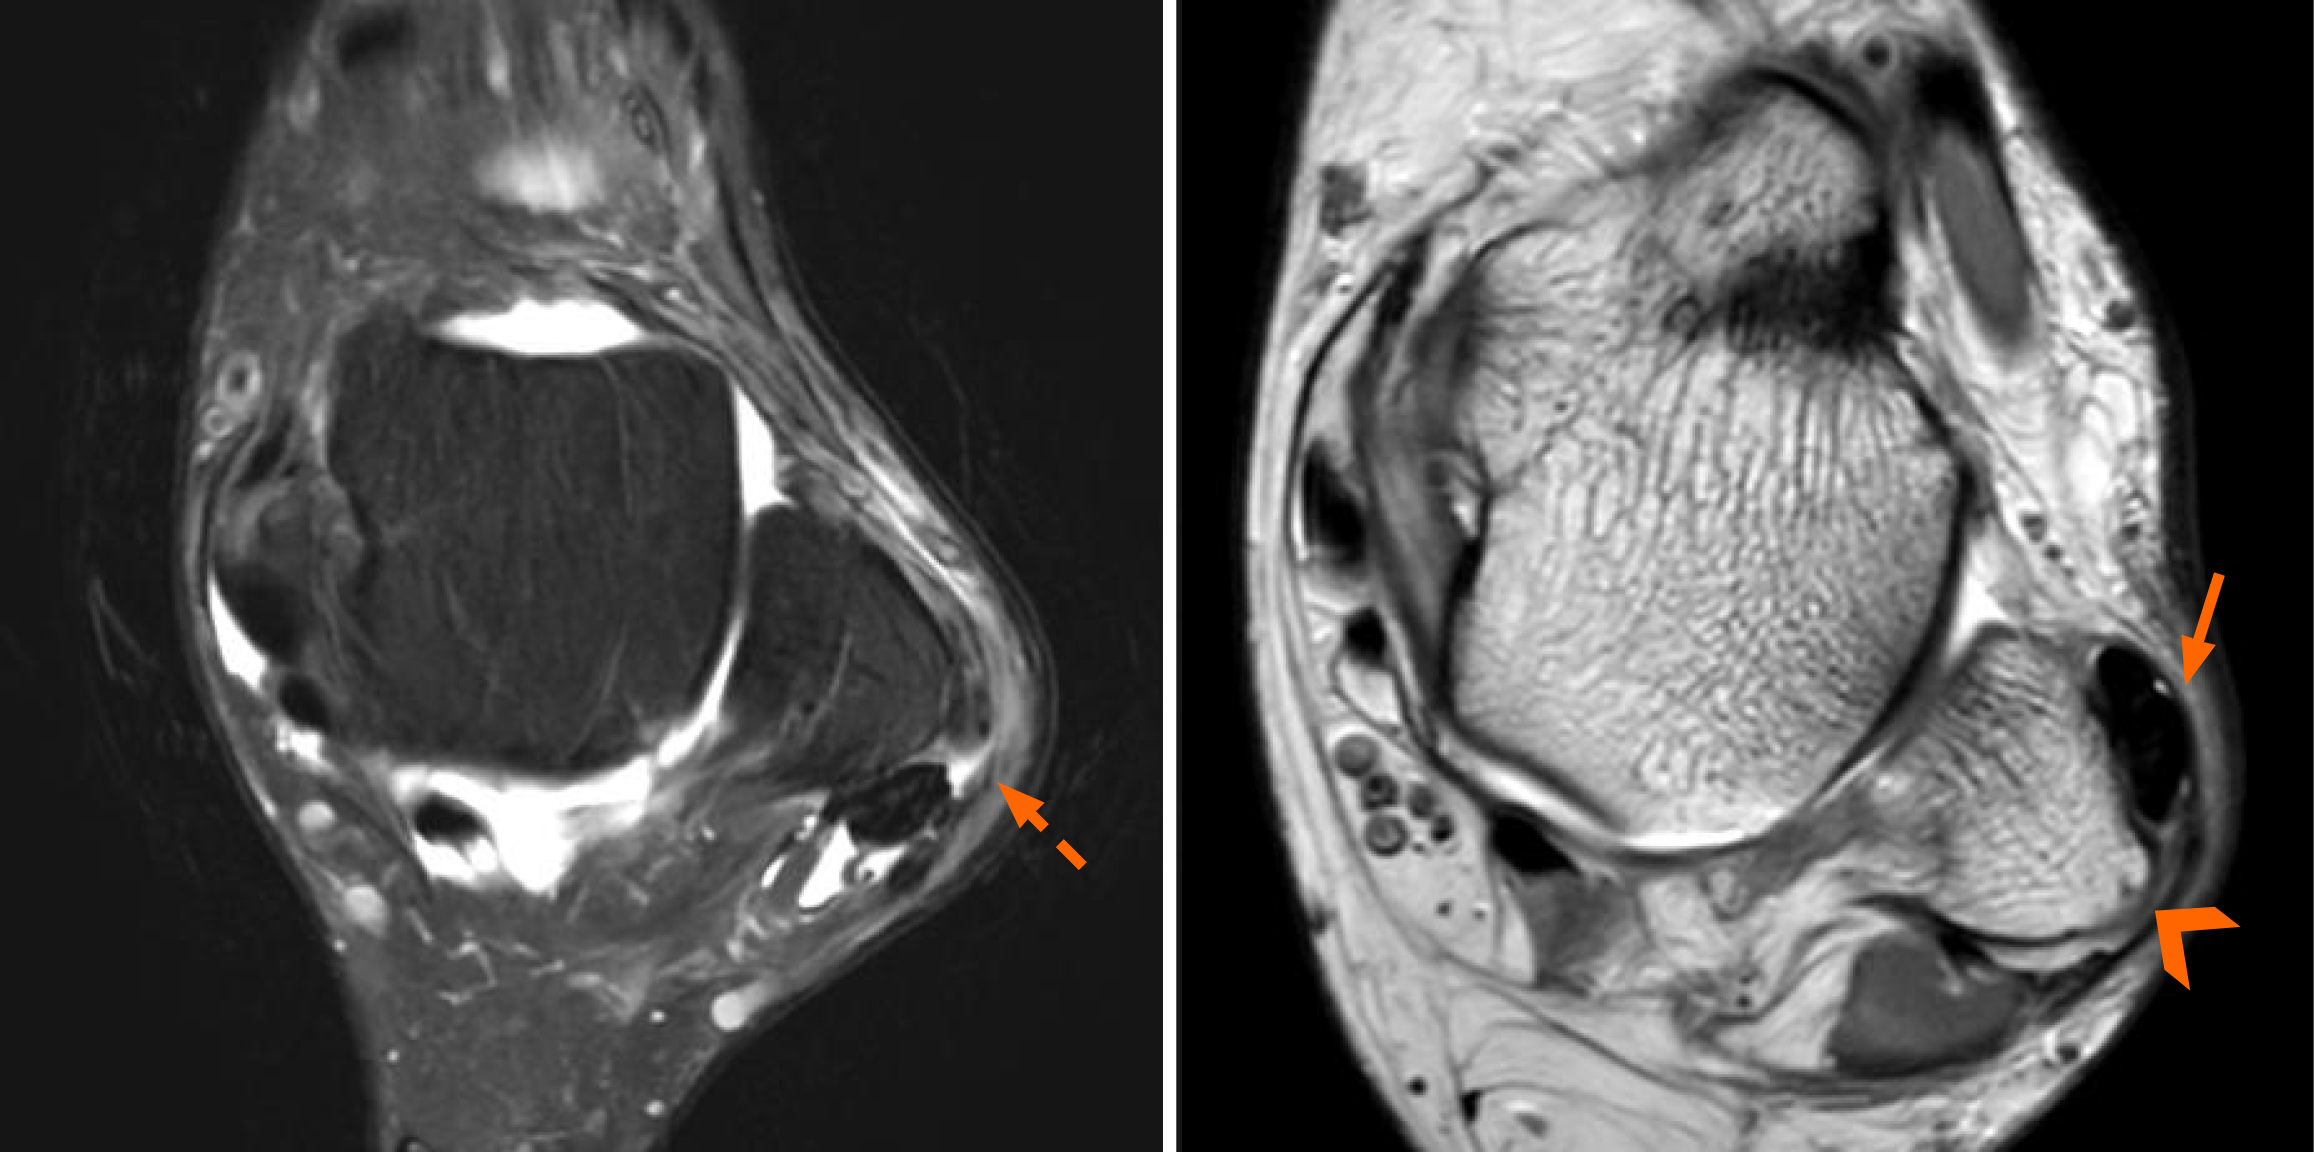

Figure 4 Magnetic resonance imaging shows dislocated peroneal tendons (arrow) and a torn superior peroneal retinaculum (dotted arrow), accompanied by a convex peroneal groove (arrowhead).